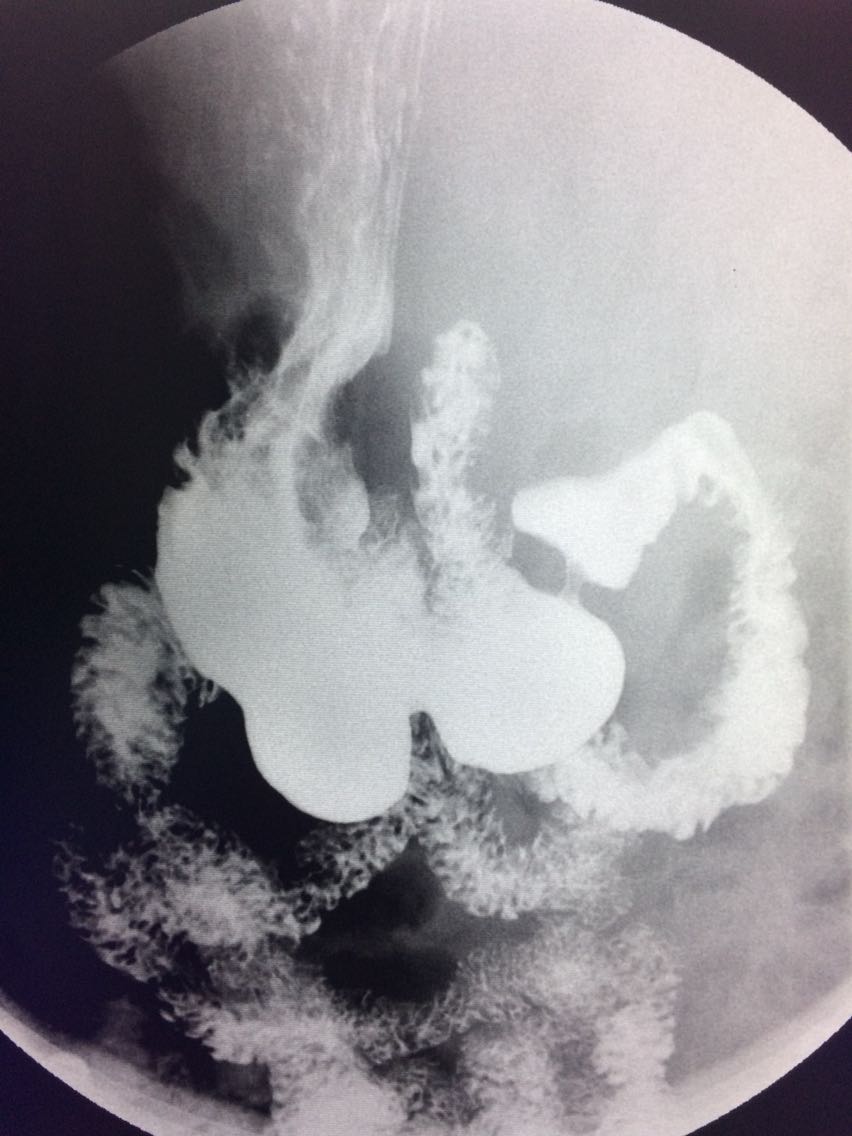

一例溃疡型胃癌。

男,45岁 反复胃疼5年余。 5年来,反复出现胃疼,进食后半小时加重,经常感觉饥饿,当地按胃溃疡,给予阿莫西林,奥美拉唑治疗,具体不详,效果欠佳,遂入院,入院来,饮食睡眠,二便可。 既往体健。 入院上消化道造影如图。

讨论,诊断及鉴别诊断? 胃溃疡的影像表现? 溃疡良恶性的鉴别? 入院后行胃大部切除术。 诊断,胃腺癌。